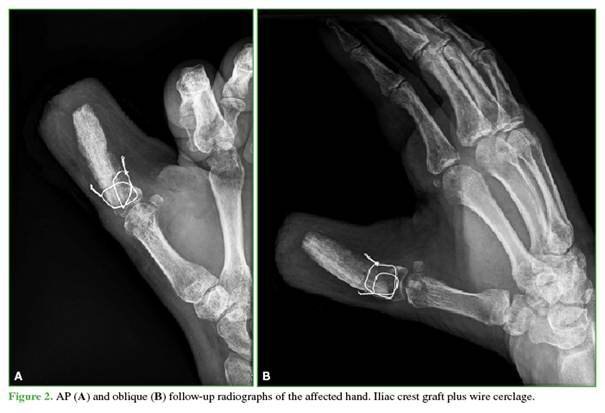

3)                  Fixation of the iliac crest graft: the graft was stabilized to the remaining base of the proximal phalanx using wire cerclage in the coronal and sagittal planes of the metacarpophalangeal joint, supplemented with temporary Kirschner wires. If tendon remnants are present, a tenoplasty may be performed; this was not required in our patient (Figure 2).